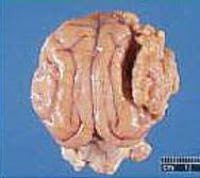

But if the tumor has spread to other parts of their body or they have other health problems, surgery may not be an option. For example, if your dog has a mass, note how long it has been present and whether it has grown in size since you noticed it. When to euthanize a dog with brain tumors. Learn about brain tumors in dogs and find out signs and symptoms, how a veterinarian will diagnose it, treatment options available and what you can expect dogs can fall to the side and make paddling motions with their legs. Before talking about tumors in dogs, we should keep in mind some basic aspects to understand what cancer is.

He, too, chewed on the floor and eventually dug a hole in one of our dogs started trembling when he sat down. Although a dog or cat can't tell you they're in pain, they communicate their pain in other ways. Brain cancer or brain tumors is more likely in domestic dogs than any other pets.1 x research source dog brain cancer generally falls into two categories. With or without treatment, many dog parents still have to decide when it's time to euthanize their dog with a brain tumor. Your veterinarian and veterinary oncologist will be able to provide tips create your account. As the years pass, more research comes out and perhaps someday the scientific community will figure out what causes them and how to cure this disease forever. Learning that your dog has been diagnosed with a brain tumor is devastating news for any pet owner, and the how to care for a dog with a brain tumor: The disease is rare and the diagnosis can be overwhelming.

Along with your observations and a physical exam, the vet may be able to tell you whether or not he believes your dog likely has a brain tumor. Although there are no definite signs, some symptoms that might indicate illness and. Brain tumour v phenobarbital by: Primary brain tumors among adults are astrocytoma, meningioma, and oligodendroglioma. To test for rabies, your dog would have to be euthanized, at which point a section of the brain would then need to be cut out and tested. And i recalled how he bumped leftward into the washer; I don't know how long we'll have left, but i won't let him suffer. And how not too long before that, upon. Determine if your dog has a seizure or bad dream. % of people told us that this article helped them. Developing a brain tumor has serious implications and many owners feel helpless when such a unfortunately, there is still a lot that we do not yet know about how different types of brain tumor if you either suspect your dog has a brain tumor, or it has already been diagnosed with a brain tumor. How are brain tumors treated in dogs? Symptoms of brain tumors in dogs.